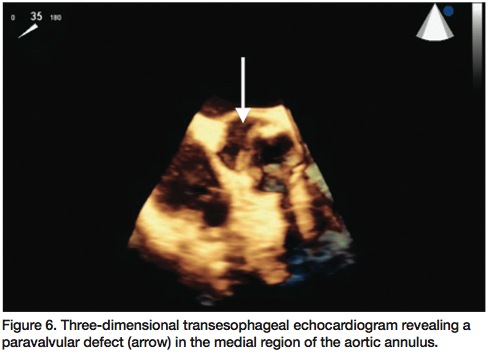

A 56-year-old male status post bioprosthetic aortic valve replacement (20 mm Edwards Lifesciences) approximately six months earlier, presented with progressive decompensated heart failure (New York Heart Association Class III, Killip Class II). Transthoracic echocardiogram demonstrated a bioprosthetic aortic valve with moderate paravalvular regurgitation, in addition to mild central

aortic insufficiency with preserved left ventricular ejection fraction of 50-55%. Three-dimensional transesophageal echocardiogram confirmed 3+ paravalvular aortic regurgitation originating from the medial region of the aortic annulus (Figure 6). The patient was then referred for percutaneous closure due to high associated mortality risk of redo sternotomy.